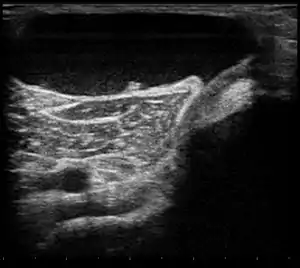

Ultrasound image of Baker's cyst

Diagnostic methodConfirmed by ultrasound or MRI[3]

Risk factors include other knee problems such as osteoarthritis, meniscal tears, or rheumatoid arthritis.[1][3][4] The underlying mechanism involves the flow of synovial fluid from the knee joint to the gastrocnemio-semimembranosus bursa, resulting in its expansion.[1] The diagnosis may be confirmed with ultrasound or magnetic resonance imaging (MRI).[3]

Diagnosis is by examination. A Baker's cyst is easier to see from behind with the patient standing with knees fully extended. It is most easily palpated (felt) with the knee partially flexed. Diagnosis is confirmed by ultrasonography, although if needed and there is no suspicion of a popliteal artery aneurysm then aspiration of synovial fluid from the cyst may be undertaken with care. An MRI image can reveal presence of a Baker's cyst.